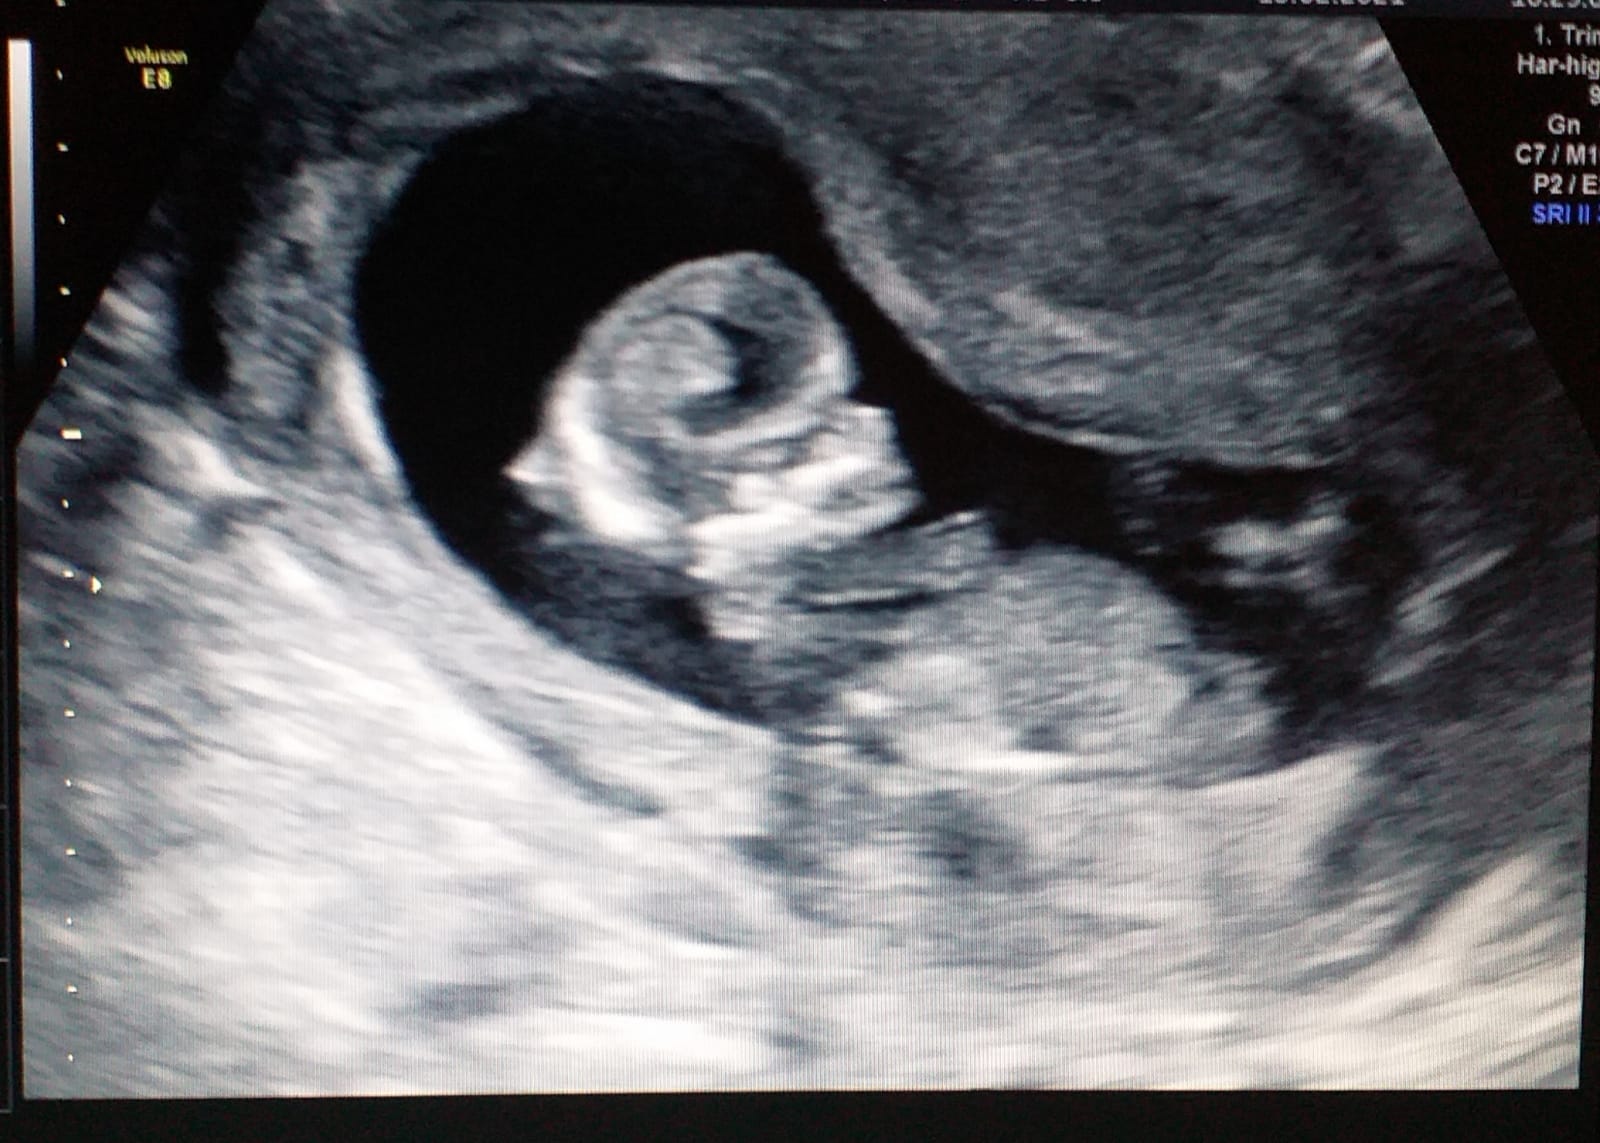

“Dios nos puso la mano, nos marcó el camino”, reflexionó emocionada. Enseguida recibieron la ecografía y hasta pudieron escuchar los latidos. Y de inmediato, se creó el vínculo con esa mujer ucraniana a través de mails y con intermediarios mediante.